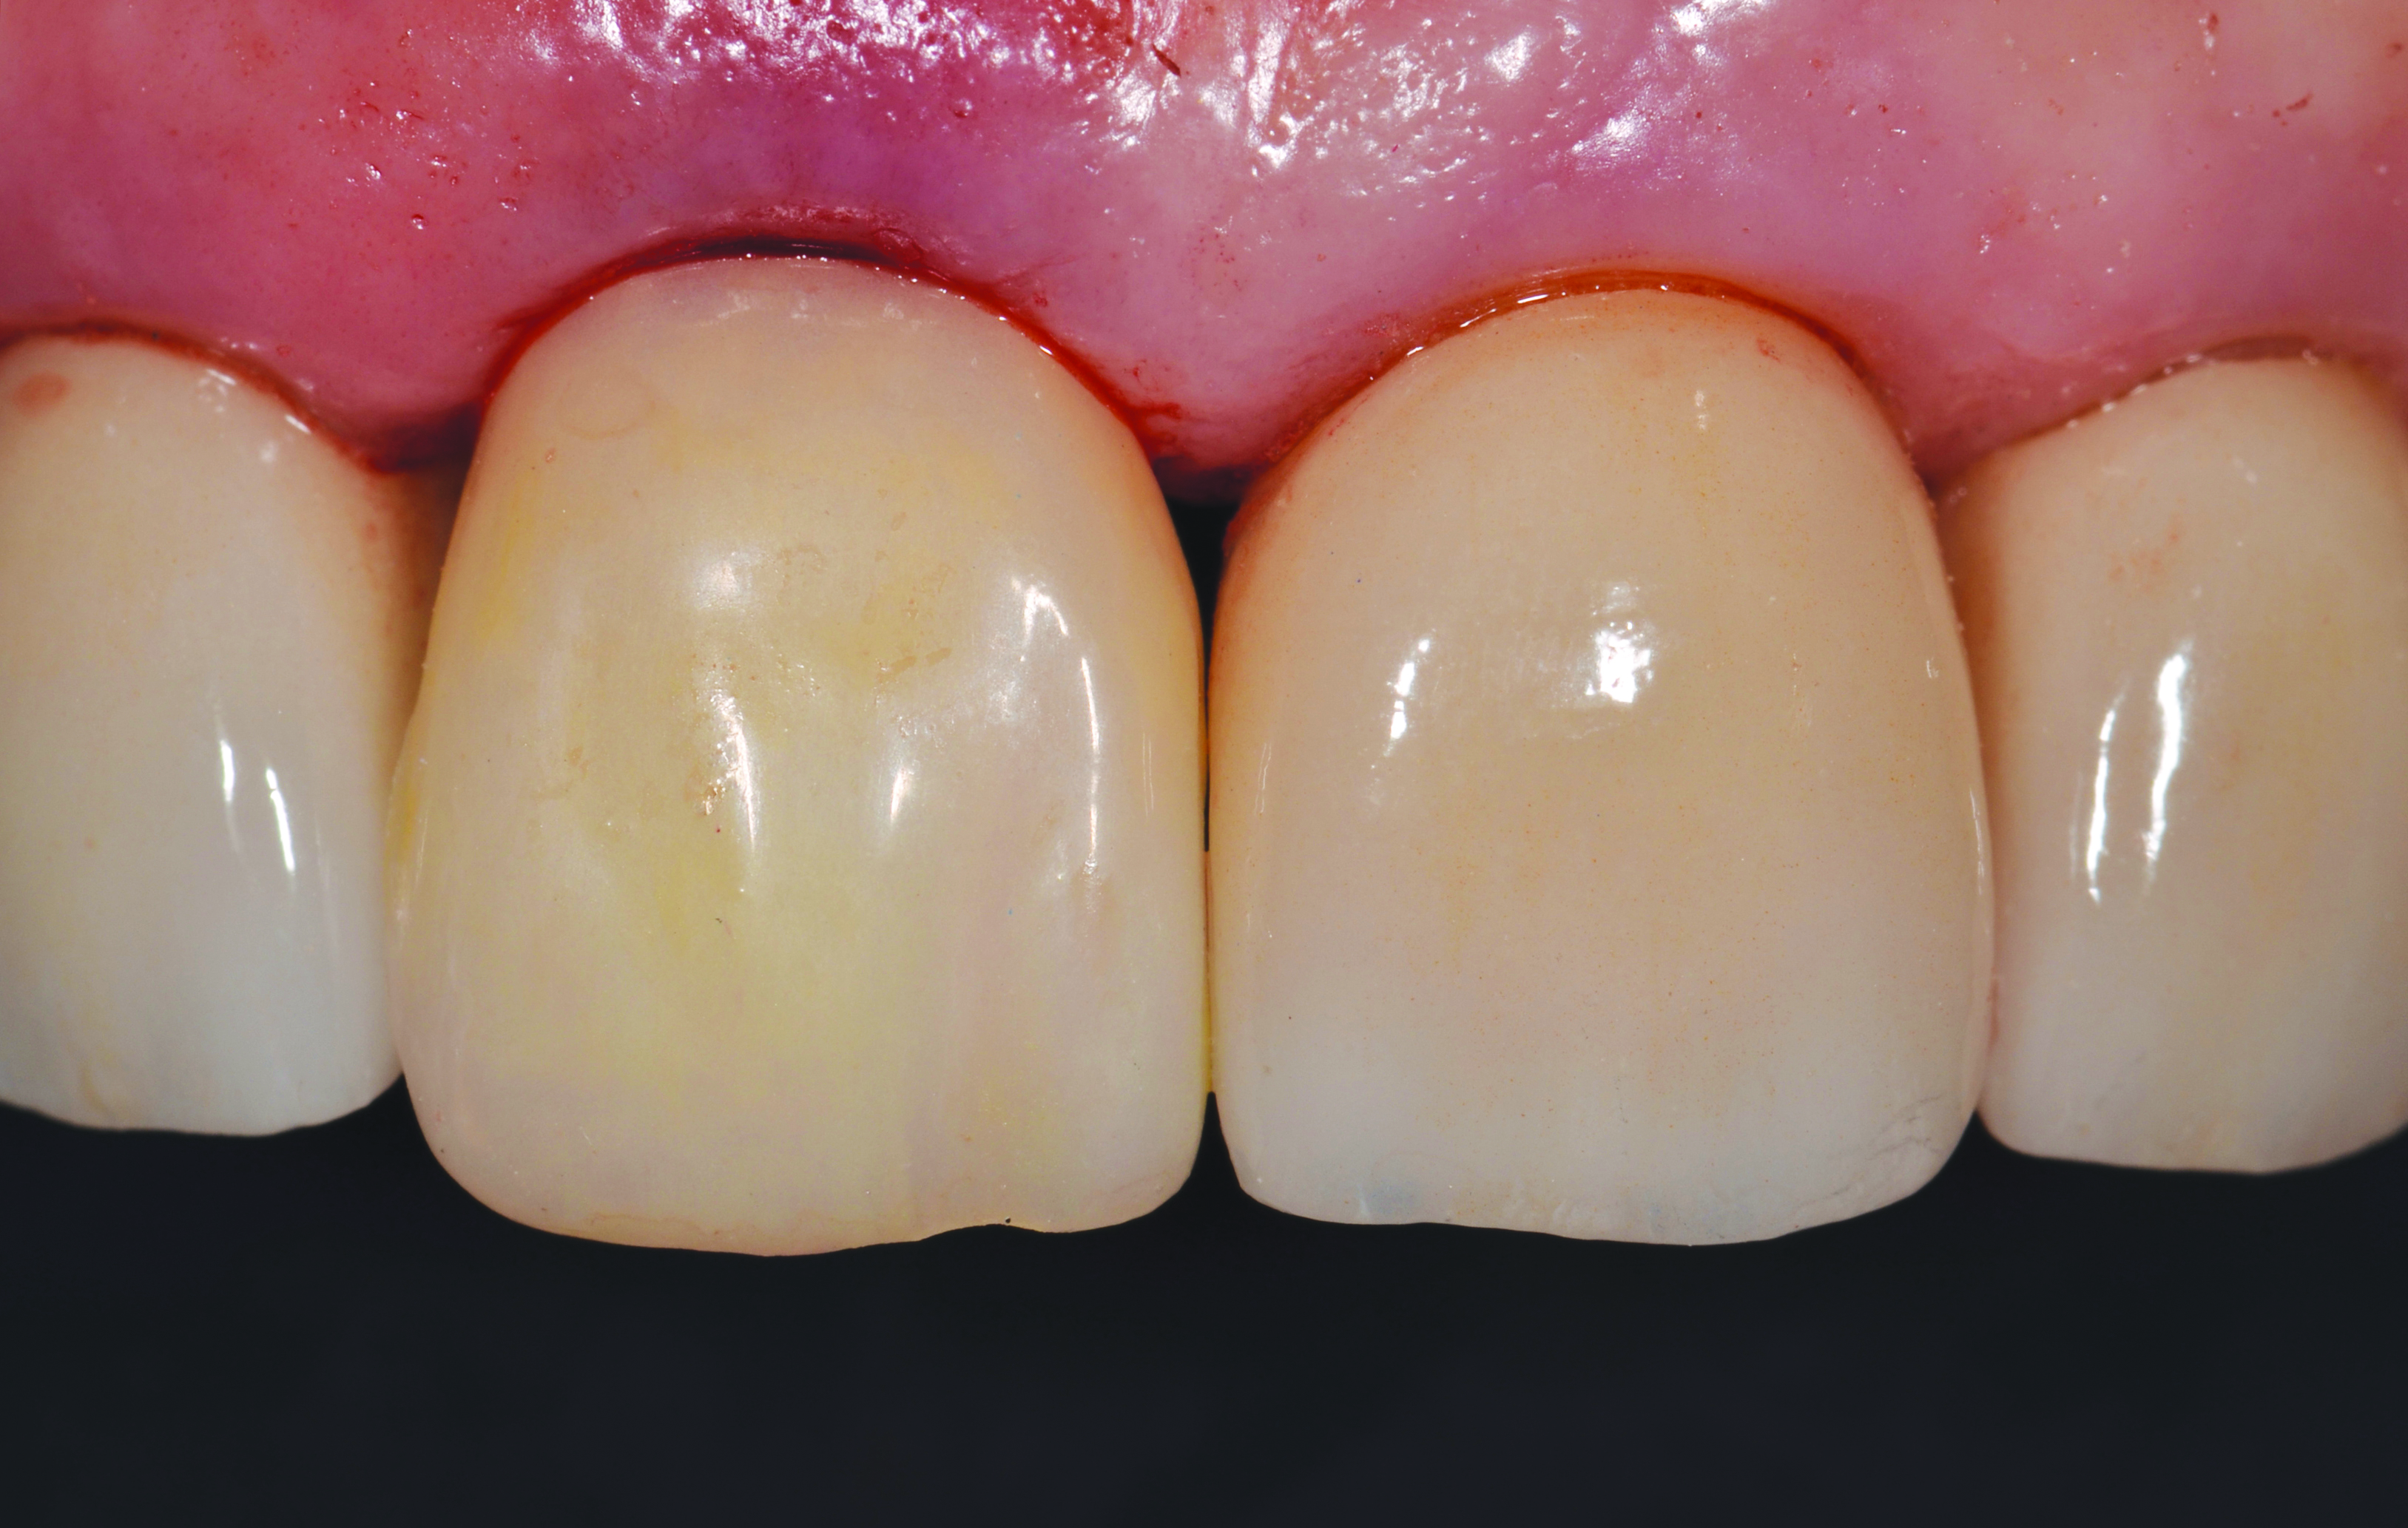

The patient returned for her surgical visit and consent was obtained. Tooth No. 8 was extracted with the aid of periotomes maintaining the integrity of the buccal plate. The socket was curetted and irrigated with sterile saline and the Simplant SAFE Guide was placed. The assessment of the surgical guide’s intimate fit to the teeth was verified by creating occlusal and proximal windows, allowing for visual inspection to assure the guide was seated (Figure 7). The OsseoSpeed EV guided surgical kit (Dentsply Sirona Implants) was used with full depth and location drilling control. The implant was placed through the guide to its proper depth (Figure 7). An insertion torque of 35 Ncm was achieved and verified by the surgical motor, allowing for adequate initial stability for immediate loading. The timing of the implant was attained by assuring the large notch on the implant driver lined up perfectly with the channel index line on the surgical guide (Figure 8 through Figure 10). Due to the immediate nature of the implant placement, a facial gap was evident between the implant and the alveolar process. A xenograft material (Bio-Oss, Geistlich Biomaterials, geistlich-na.com) was placed to fill this gap according to established protocols.14 The Atlantis custom abutment was then placed in its proper position and the seating was verified with digital radiography. The abutment was torqued to 25 Ncm, as per the manufacturer’s specifications (Figure 11). The interim prosthesis was then placed onto the abutment and slight adjustments were made. A final custom stain and glaze was placed on the interim prosthesis crown using Lite Art coloring pastes (Shofu Dental Corporation, shofu.com). The provisional was cemented with TempBond NE (Kerr, kerrdental.com) and was relieved of any excursive contacts. The patient was given post-operative instructions and left in extremely high spirits (Figure 12).